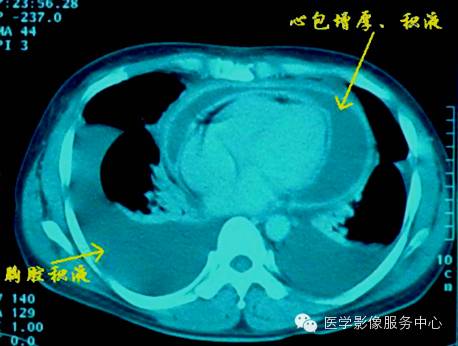

CT表现为:包腔增宽,心包腔内液体呈水样密度。CT值介于12HU~40HU之间,血性及渗出液CT值较漏出液及乳糜液CT值较低。少量积液仰卧位主要集中在左室背侧,中量积液对扩展至心脏腹侧,大量积液时可包裹所会心脏及大血管根部,下界可达BNJ水平,心包壁层、脏层间距明显增宽。

一般将心包积液分为三度,

I度为少量积液.积液量小于100ml,舒张期心包脏、壁层间距5mm~15mm;

II度为中等量积液,积液量100ml~500ml。心包脏、壁层间距15mm~25mm;

III度为大量积液,积液量>500ml,心包脏、壁层间距>25mm。